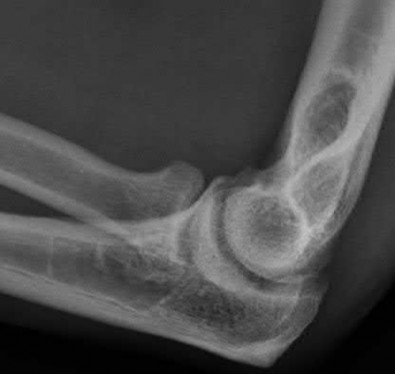

A patient has an elbow injury that includes a coronoid fracture, medial collateral ligament injury, and a radial head fracture. When is excision of the radial head without replacement indicated as definitive treatment for the radial head injury?

Excision is generally not indicated in this clinical scenario Corrent answer: 5

The injury likely represents a terrible triad injury. Restoration of the lateral column is required to restore valgus stability. A repaired or replaced radial head is also thought to be protective of the coronoid fracture repair. Therefore, excision is not indicated. Either radial head arthroplasty or open reduction and internal fixation would be indicated.